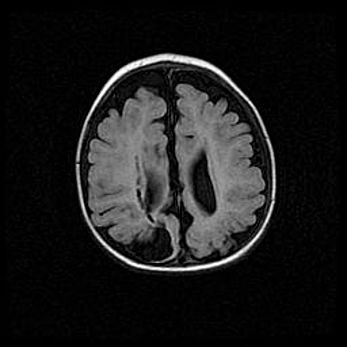

Лейкомаляция с кистозно-глиозной дегенерацией головного мозга.

Возраст: 2 месяца 25 дней

Вес: 6400 г

Окружность головы: 40 см

Срок гестации: 41 неделя

Лейкомаляцию относят к ишемически-гипоксическим повреждениям головного мозга, диагностируемым у новорожденных. При лейкомаляции в головном мозге обнаруживают очаги некроза, возникшие после тяжелой гипоксии и нарушения кровотока. В процессе морфогенеза очаги проходят три стадии: 1) развития некроза, 2) резорбции и 3) формирования глиозного рубца или кисты. Перивентрикулярная лейкомаляция (ПЛ) встречается примерно в 12% случаев среди новорожденных, обычно – у недоношенных детей, причем, частота ее зависит от массы, с которой младенец появился на свет. Наибольшее число малышей страдает лейкомаляцией, если масса при рождении 1500-2500 г.